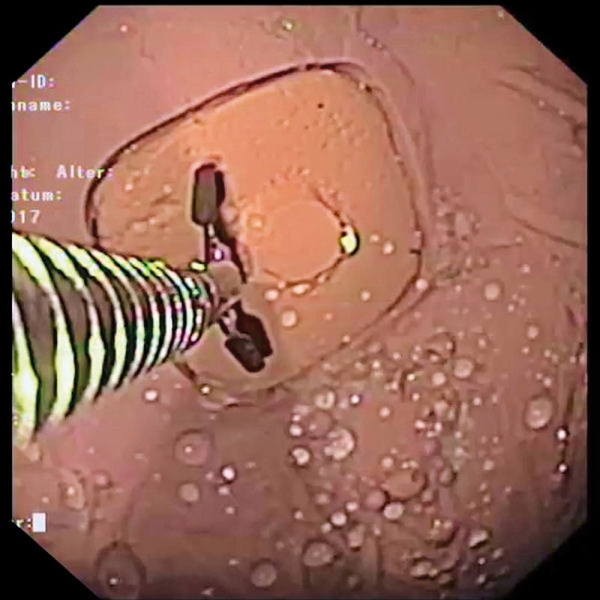

- Odstranjevanje tkiva s hladno zanko, npr. polipektomija

- Odvzem biopsije tkiva s kleščami